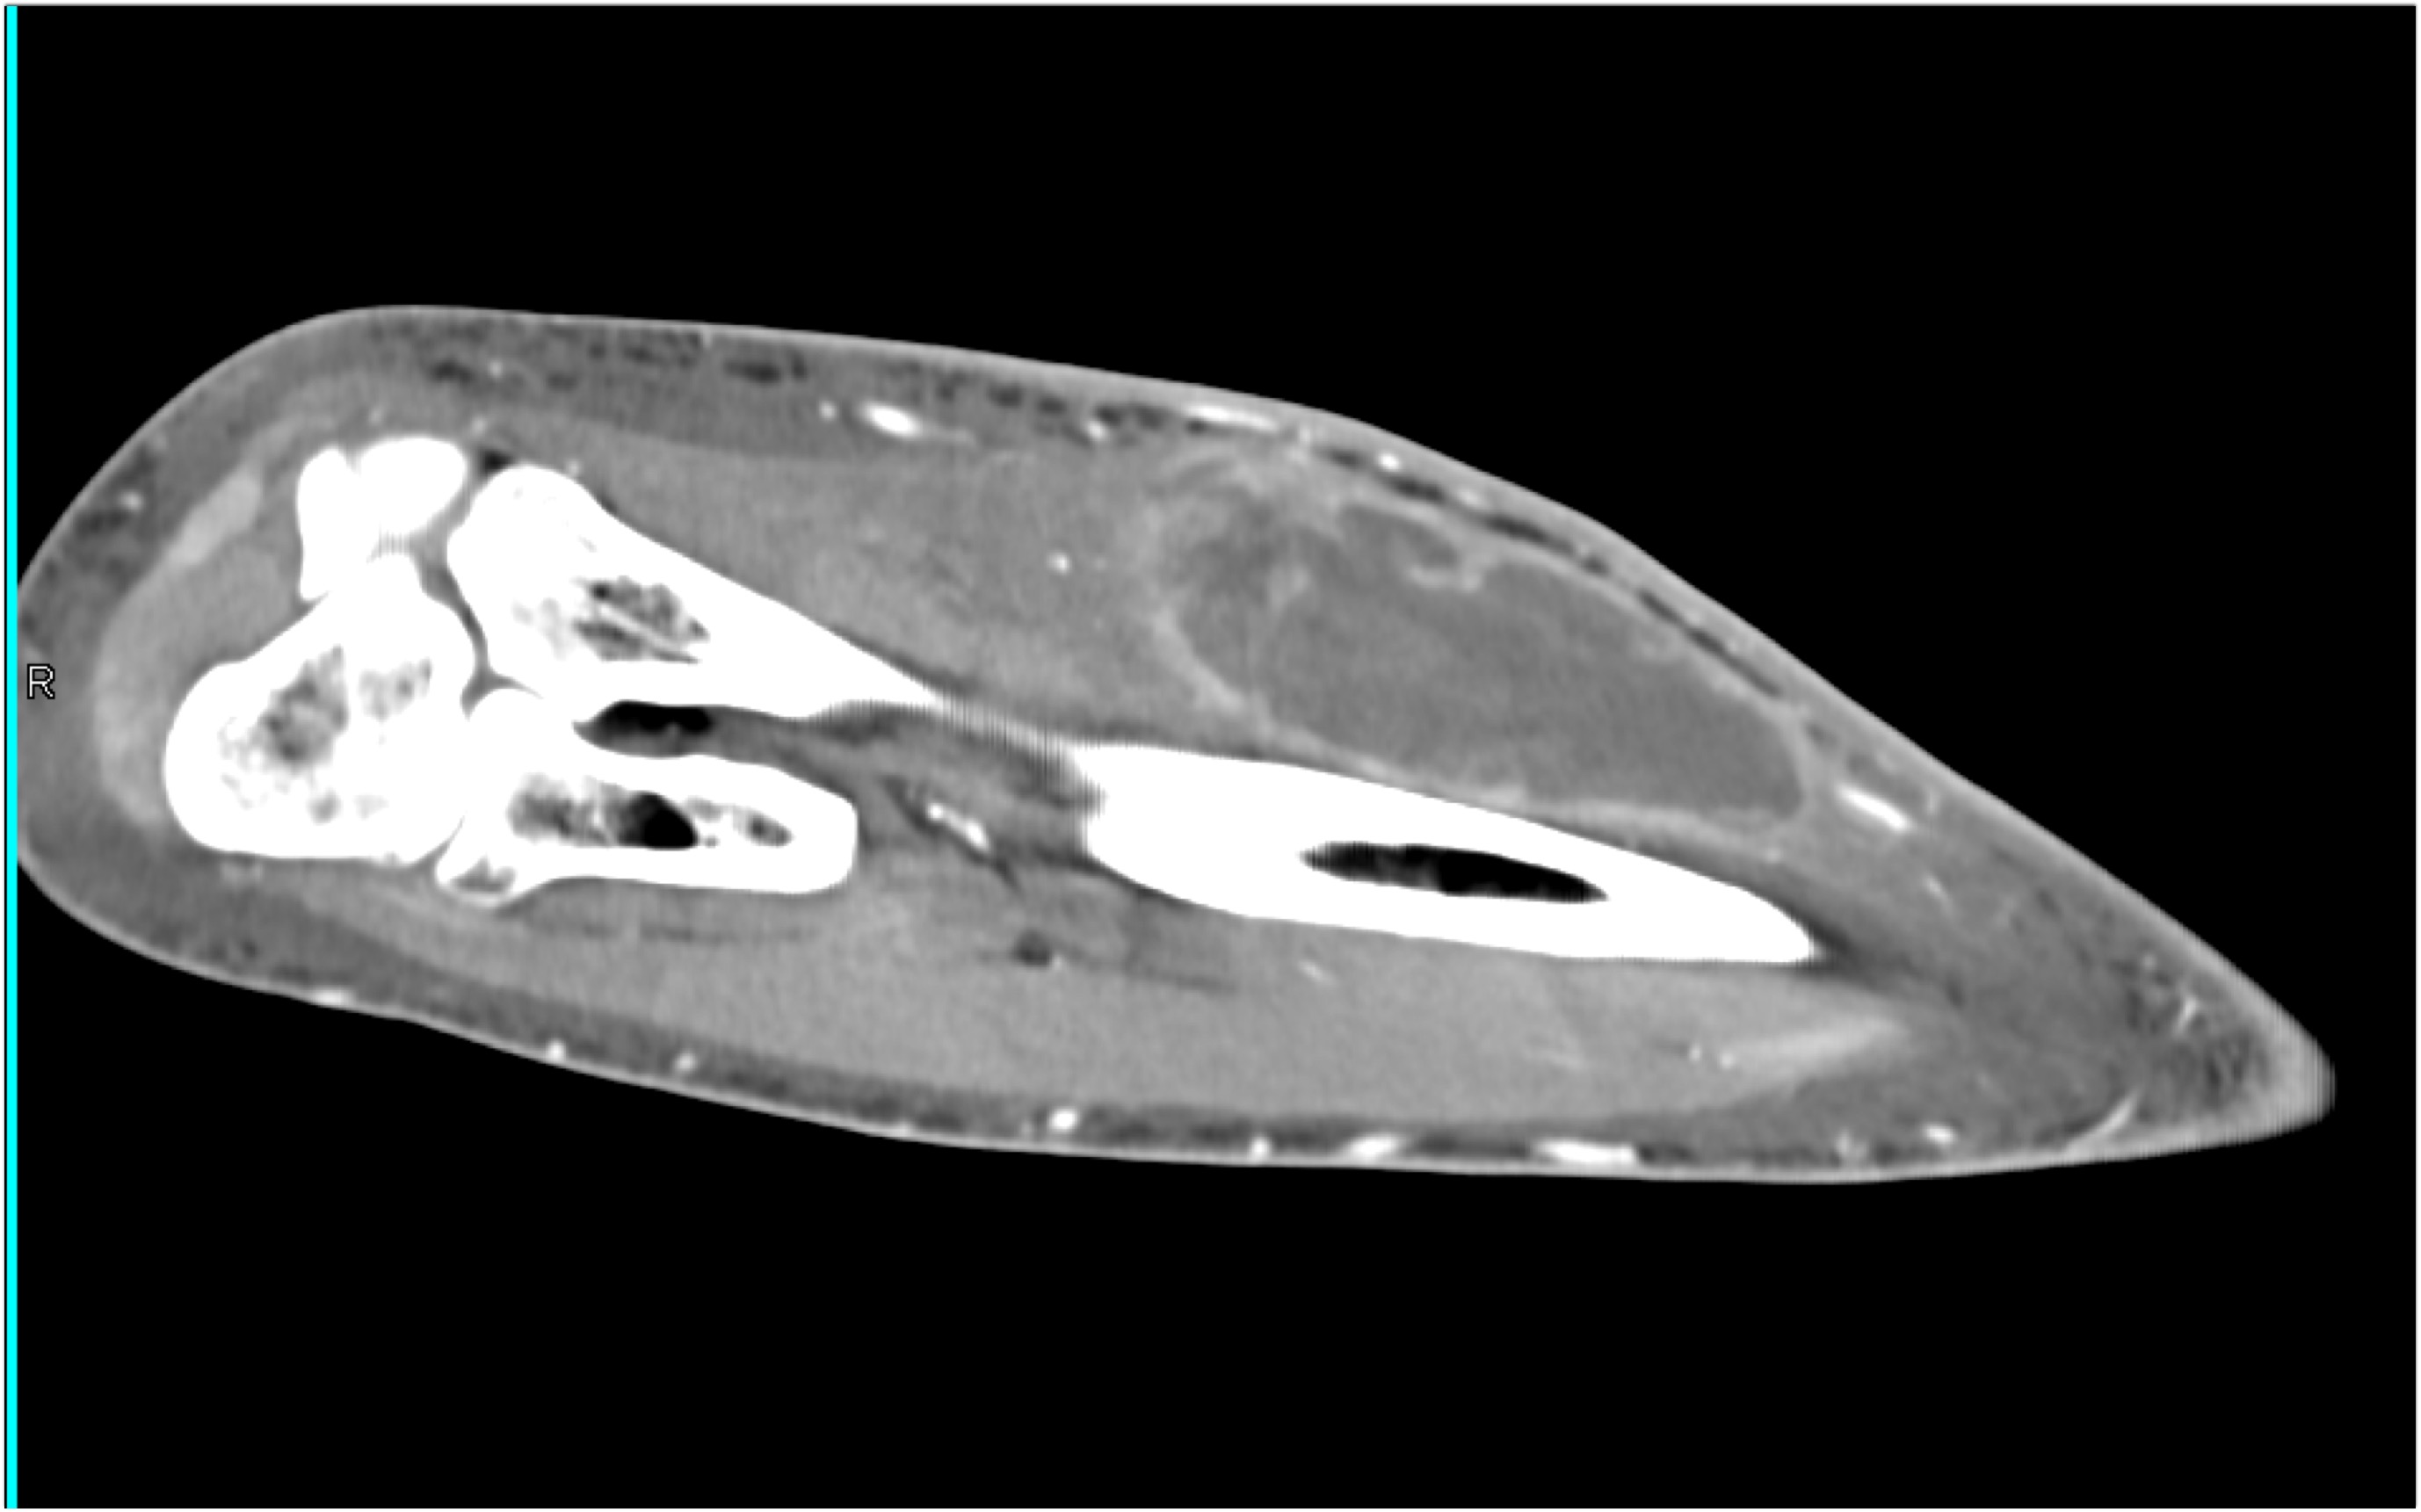

5) In this painful forearm the most likely diagnosis is?

acute bleed (hematoma)

abscess

sarcoma

infarction